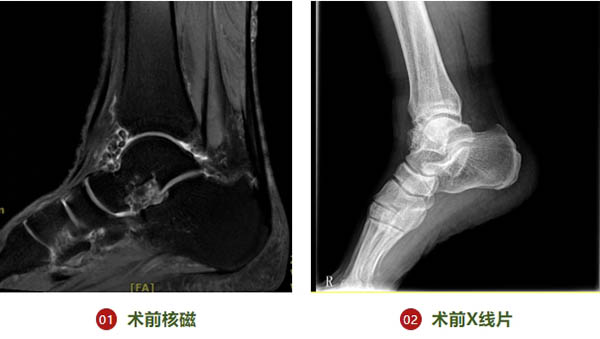

医院骨二科(矫形与关节科)近期治疗一例踝关节滑膜软骨瘤患者。于XX,男,68岁,年轻时为足球爱好者。右足踝疼痛伴背屈活动受限2月余。自诉2月余前无明显诱因出现右足踝活动时足外侧及外踝区域疼痛不适,活动受限。未予特殊治疗,症状持续不能缓解,就诊于我院门诊,行右踝核磁检查提示:2023-11-09 踝关节MRI(R右侧),1、右踝关节腔多发游离体,考虑滑膜软骨瘤病,右踝关节腔少量积液;2、右踝关节退行性改变;胫骨下段少许骨髓水肿(图1,2)。